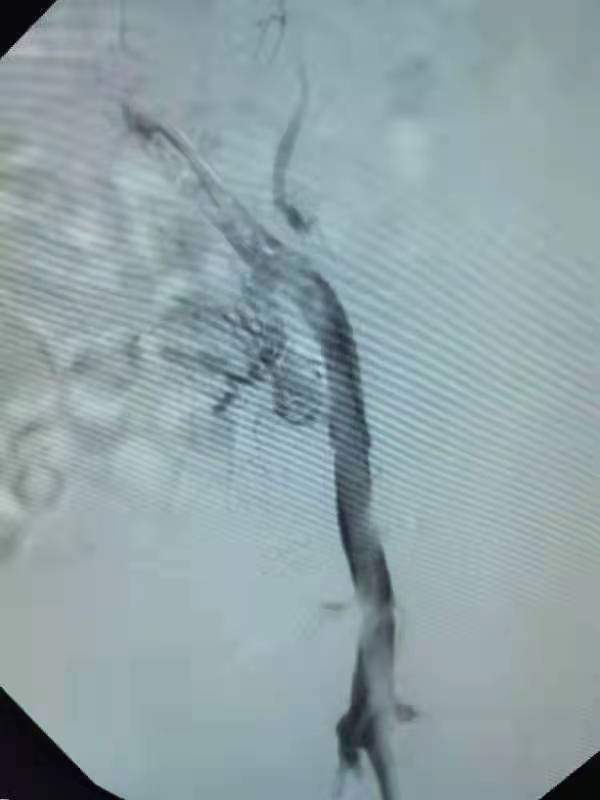

术前许玉华主任团队制定了详细的诊疗计划和周密的手术方案,术中造影示:左侧髂总静脉、左侧髂内静脉、左侧髂外静脉见多发充盈缺损,造影剂回流下腔静脉不畅,予以碎栓、抽栓术,抽出大量的血栓。术后,患者下肢水肿减轻。